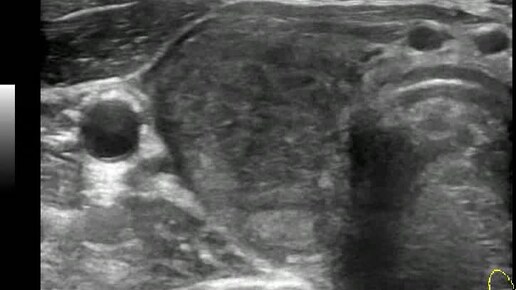

Видео к статье "Стратификация узлов щитовидной железы. TI-RADS-4" https://dzen.ru/a/ZwNx-uQp-Sfk6L46

Ультразвуковые находки от врача УЗД Зорина Я.П.